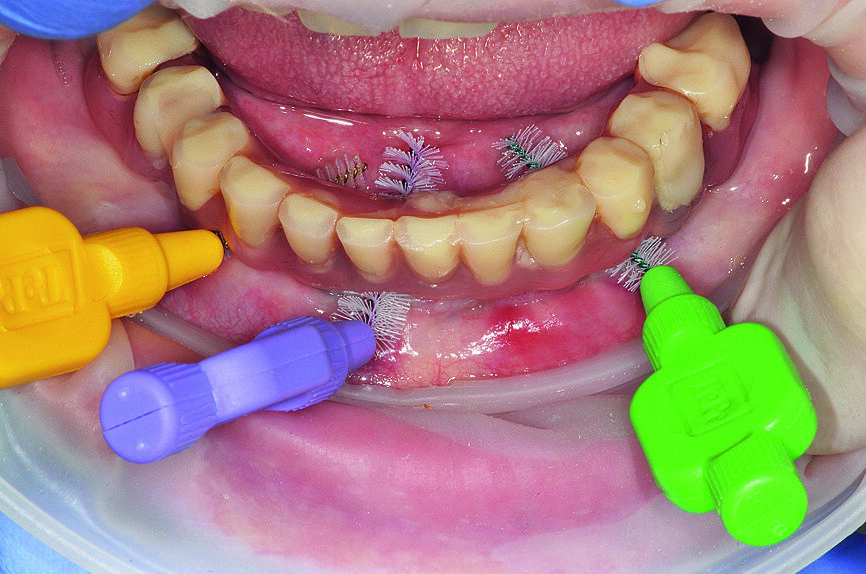

| Figs. 4a : Soins péri-implantaires à domicile avec AirFloss (Philips),

Fig. 4b : Soins péri-implantaires à domicile avec X-Floss (ROEN)

Fig. 4 c : Soins péri-implantaires à domicile avec brossette interdentaire (TePe).

Pour assurer des soins professionnels minimalement invasifs, le port de loupes binoculaires ainsi que l’utilisation d’agents révélateurs de plaque et de dispositifs adaptés sont requis, particulièrement si l’entretien de la restauration prothétique est une tâche ardue pour le patient. L’élimination adéquate et périodique du biofilm doit être considérée comme la norme de traitement en termes de prévention et de prise en charge de la péri-implantite.11 Pour cette raison, les patients doivent être motivés et informés sur la manière d’entretenir quotidiennement les implants. Cette approche devrait commencer avant la procédure implantaire et se poursuivre après le traitement, dans le cadre de visites de rappel régulières et personnalisées (Figs. 4 et 5).